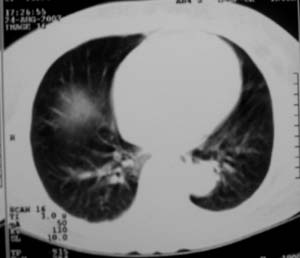

以下是引用zjzjr在2007-8-30 22:22:00的发言:[br]右上肺肺囊肿合并感染.右下肺肺大泡.左肺舌段感染.